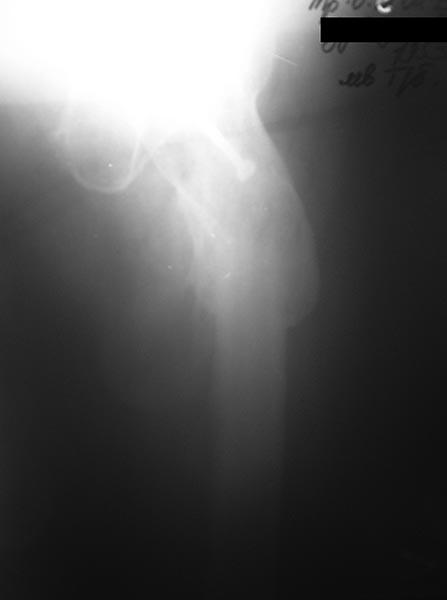

Re: сросшийся с варусной деформацией проксимальный отдел левого бедра

Уважаемый Ю.В, технически возможны все три варианта: 1,2 и 3. Только не совсем понимаю, зачем нужен третий, и в чем преимущества 2-го перед 1-ым? Нужно очень тщательное предоперационное планирование. Одной, представленной, передне-задней рентгенограммы для этого недостаточно. Да и вообще,для конструктивной помощи информации мало.

Есть еще распространенная в советские времена медиализирующая вальгизирующая остеотомия с фиксацией пластиной типа Петрулиса Петуховой или пластиной Цито. Мне кажется важно исправить деформацию, а чем зафиксировать дело предпочтений и логики хирурга. Но в данном случае не понятно как данная рентгенкартинка соотносится с клиникой , ведь при таких р-граммах может ничего не беспокоить пациента и тогда операция не имеет необходимости. Как часто бывает на форуме представляется мало данных. Но ведь мы лечим не р-грамму, а пациента, и представлять только р-грамму не описывая клинику не совсем корректно, особенно при испрашивании совета у коллег. Если представляется р-грамма, как в данном случае, то хотя бы 2 проэкции. Решение по данному вопросу может зависеть от функции т/б сустава, а на Ваших р-граммах даже в одной проэкции его сложно оценить. Следовательно вопрос о протезировании не может быть однозначно решен.

Согласен с Алексеем, вопрос "возможна ли?" тут не самый актуальный. Как говорится, возможно все, что не противоречит фундаментальным законам мироздания. Наверно, подразумевается все-таки другой вопрос - что предпочесть?

Надо тщательно спланировать коррекцию, как Алексей уже сказал. Сделать снимки обоих бедер на протяжении, посмотреть, что с длиной. Наложить проксимальные отделы бедер друг на друга, посмотреть, на каком уровне на сколько отклонилось.

Преимуществом внутрикостной фиксации и чрескостного остеосинтеза будет возможность сделать открытый клин, выигрыш в длине можно получить. Вариант с пластиной и минус-клином вполне рабочий. Наверно, есть клиники, где и сегодня предпочтут аппаратом исправлять. Можно вторым этапом заштифтовать. Вот как-то так в итоге хорошо бы, чтобы выглядело.

Планирую заштифтовать с клином основанием кнаружи, за одну сессию. Возможно ли это при наступившей ретракции мышц?

С тем, ЧТО собрались сделать - более-менее понятно. Как уже говорилось, возможно все... В том числе, и открытый клин основанием кнутри, что IMHO предпочтительнее. Есть другой вопрос - как делать?

Вы бы показали на скиаграммах предоперационное планирование, что куда переместится, что получится с длиной? Можно было бы более предметно обсудить, стоит ли делать именно так, и если да, то как.

Добрый вечер, Уважаемые коллеги. В подобных случаях, для фиксации после остеотомий хорошо зарекомендовали себя PFNa и DCHS. Единственно, что хочется отметить, так это остеопороз шейки и головки бедра. В подобном случае у нас была нестабильность остеосинтеза и пришлось делать эндопротезирование, причём используя ревизионную ножку Вагнера. Я бы рекомендовал сначала провести курс терапии остеопороза - (Бивалос+препараты кальция), в течении месяцев 3-х, а затем уже думать об операции. Творческих успехов.

(видимо неправильно была выбрана конструкция или технические ошибки при установке). Каково состояние мягких тканей после АВФ? Судя по состоянию костной ткани мне кажется о протезировании думать ещё рано, поносят её ещё родные ноги. В остальном полностью согласен с Алексей Юрьевичем (Семенистым) и Александром Николаевичем Челноковым, который для Вас практически и предоперационное планирование провёл, придерживался бы такой же тактики. Угол открытый кнаружи представляю с трудом, либо идёте заведомо на ещё большее укорочение, либо будет большой костный дефект.

При реконструкции проксимального бедра стандартным исследованием является прямой таз и снимок на всю длину конечности. Отдельно тазобедренный сустав в отведении и в приведении, где смотрим наличие мобильности сустава, иначе ретрагированные мышцы или неподвижный сустав не даст положительный результат даже после хорошей коррекции.